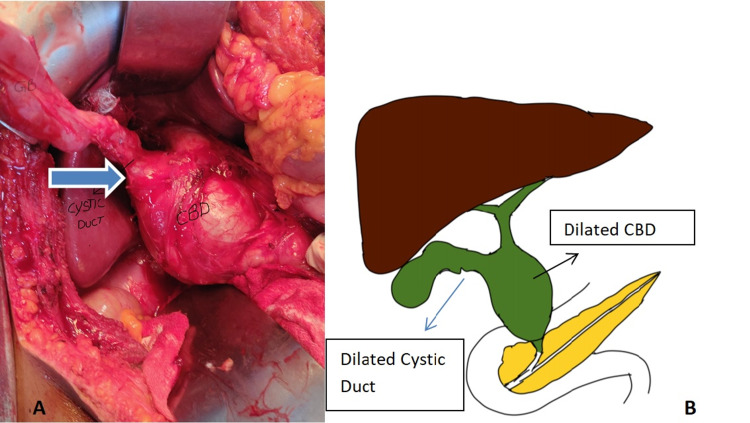

Intraoperatively gall bladder was mildly distended with no calculi. Cystic dilatation of suprapancreatic part of CBD around 6 cm in largest dimension with dilated and tortuous cystic duct of around 2 cm opening into it (Figure 2).

So in our first case, there was dilatation of both cystic duct and CBD without the involvement of common hepatic duct similar to the case of Bhoil et al., and thus, we label it as a type 6B variant. And in our second case which had isolated cystic dilatation is classified as type 6A. Management of type 6A is simple cholecystectomy if the opening of the cystic duct into CBD is narrow, whereas complete excision of CBD is required as there is a wide opening with the CBD. So this classification is important as the management of type 6A is simple cholecystectomy and type 6B is complete excision of CBD with hepaticojejunostomy.